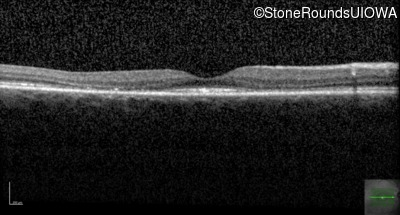

Cone and Cone Rod Dystrophy (IA1b)

Age at visit: 49 years

This 49 year old woman first experienced some loss of central vision in her left eye at age 44.